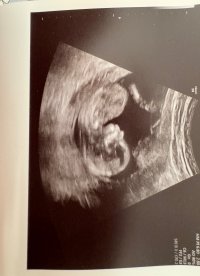

Kan se ut som jente, men veldig vanskelig å se på bildeneNoen som vil gjette kjønn? Uke 14+2